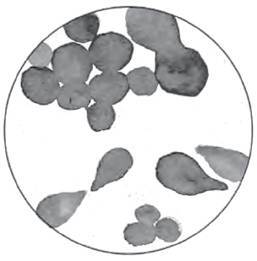

И C. albicans, и C. auris относятся к отделу подцарства высших грибов Ascomycota – разнообразной группе, в которую входят те самые «Пальцы мертвеца», сморчки, формой напоминающие мозг, и нежные алые эльфовы чаши. Внутри Ascomycota есть меньшая группа, называемая Saccharomycotina, или дрожжи, куда входит и Candida. Некоторые из них имеют близкое родство, а другие – отдаленное. Дрожжи Candida представляют собой необычное собрание живых организмов, которое принято описывать как «мусорную корзину, в которой находятся сотни видов, мало связанных друг с другом»7. Чтобы подчеркнуть разницу между этими «родственниками», один ученый сказал мне, что C. auris и C. albicans отличаются друг от друга так же, как люди от рыб. Если и есть что-то общее у разных видов дрожжей, так это их склонность существовать в виде одиночных клеток, подобно бактериям, но с небольшим количеством или отсутствием характерных признаков, из-за чего трудно отличить один вид от другого, пока не удастся собрать их в колонии на чашке Петри. Колони появляются, когда дрожжи размножаются миллионами. Чаще всего это происходит бесполым путем8: клетки отпочковываются от клонов, удваивая популяцию каждые сто минут или около того, – такой жизненный цикл больше свойствен бактериям, чем грибам. В редких случаях дрожжи ведут себя более типично для грибов: выращивают гифы или размножаются половым путем – для этого необходимы определенные условия. Способность к половому или бесполому размножению характерна для многих, если не для всех грибов, однако некоторые предпочитают только один вид, а другие могут их чередовать. Грибы фантастически разнообразны в вопросах размножения9: у каждого есть тысячи различных «типов спаривания». Когда дрожжи спариваются, их обычно круглые тела вытягиваются и становятся похожими на «шму» – это мультяшный персонаж середины XX века, который впервые появился в комиксе «Лил Эбнер». Сексуально восприимчивые «шму» притягиваются друг к другу с помощью химических запахов, называемых феромонами. Когда дрожжи культивируются в чашке Петри, невидимые клетки со временем собираются в скопления размером с булавочные уколы, которые после превращаются в округлые холмики или плоские диски, похожие на брызги краски. Колонии C. auris обычно имеют кремовый или белый цвет, но в некоторых средах приобретают оттенки розового или фиолетового.